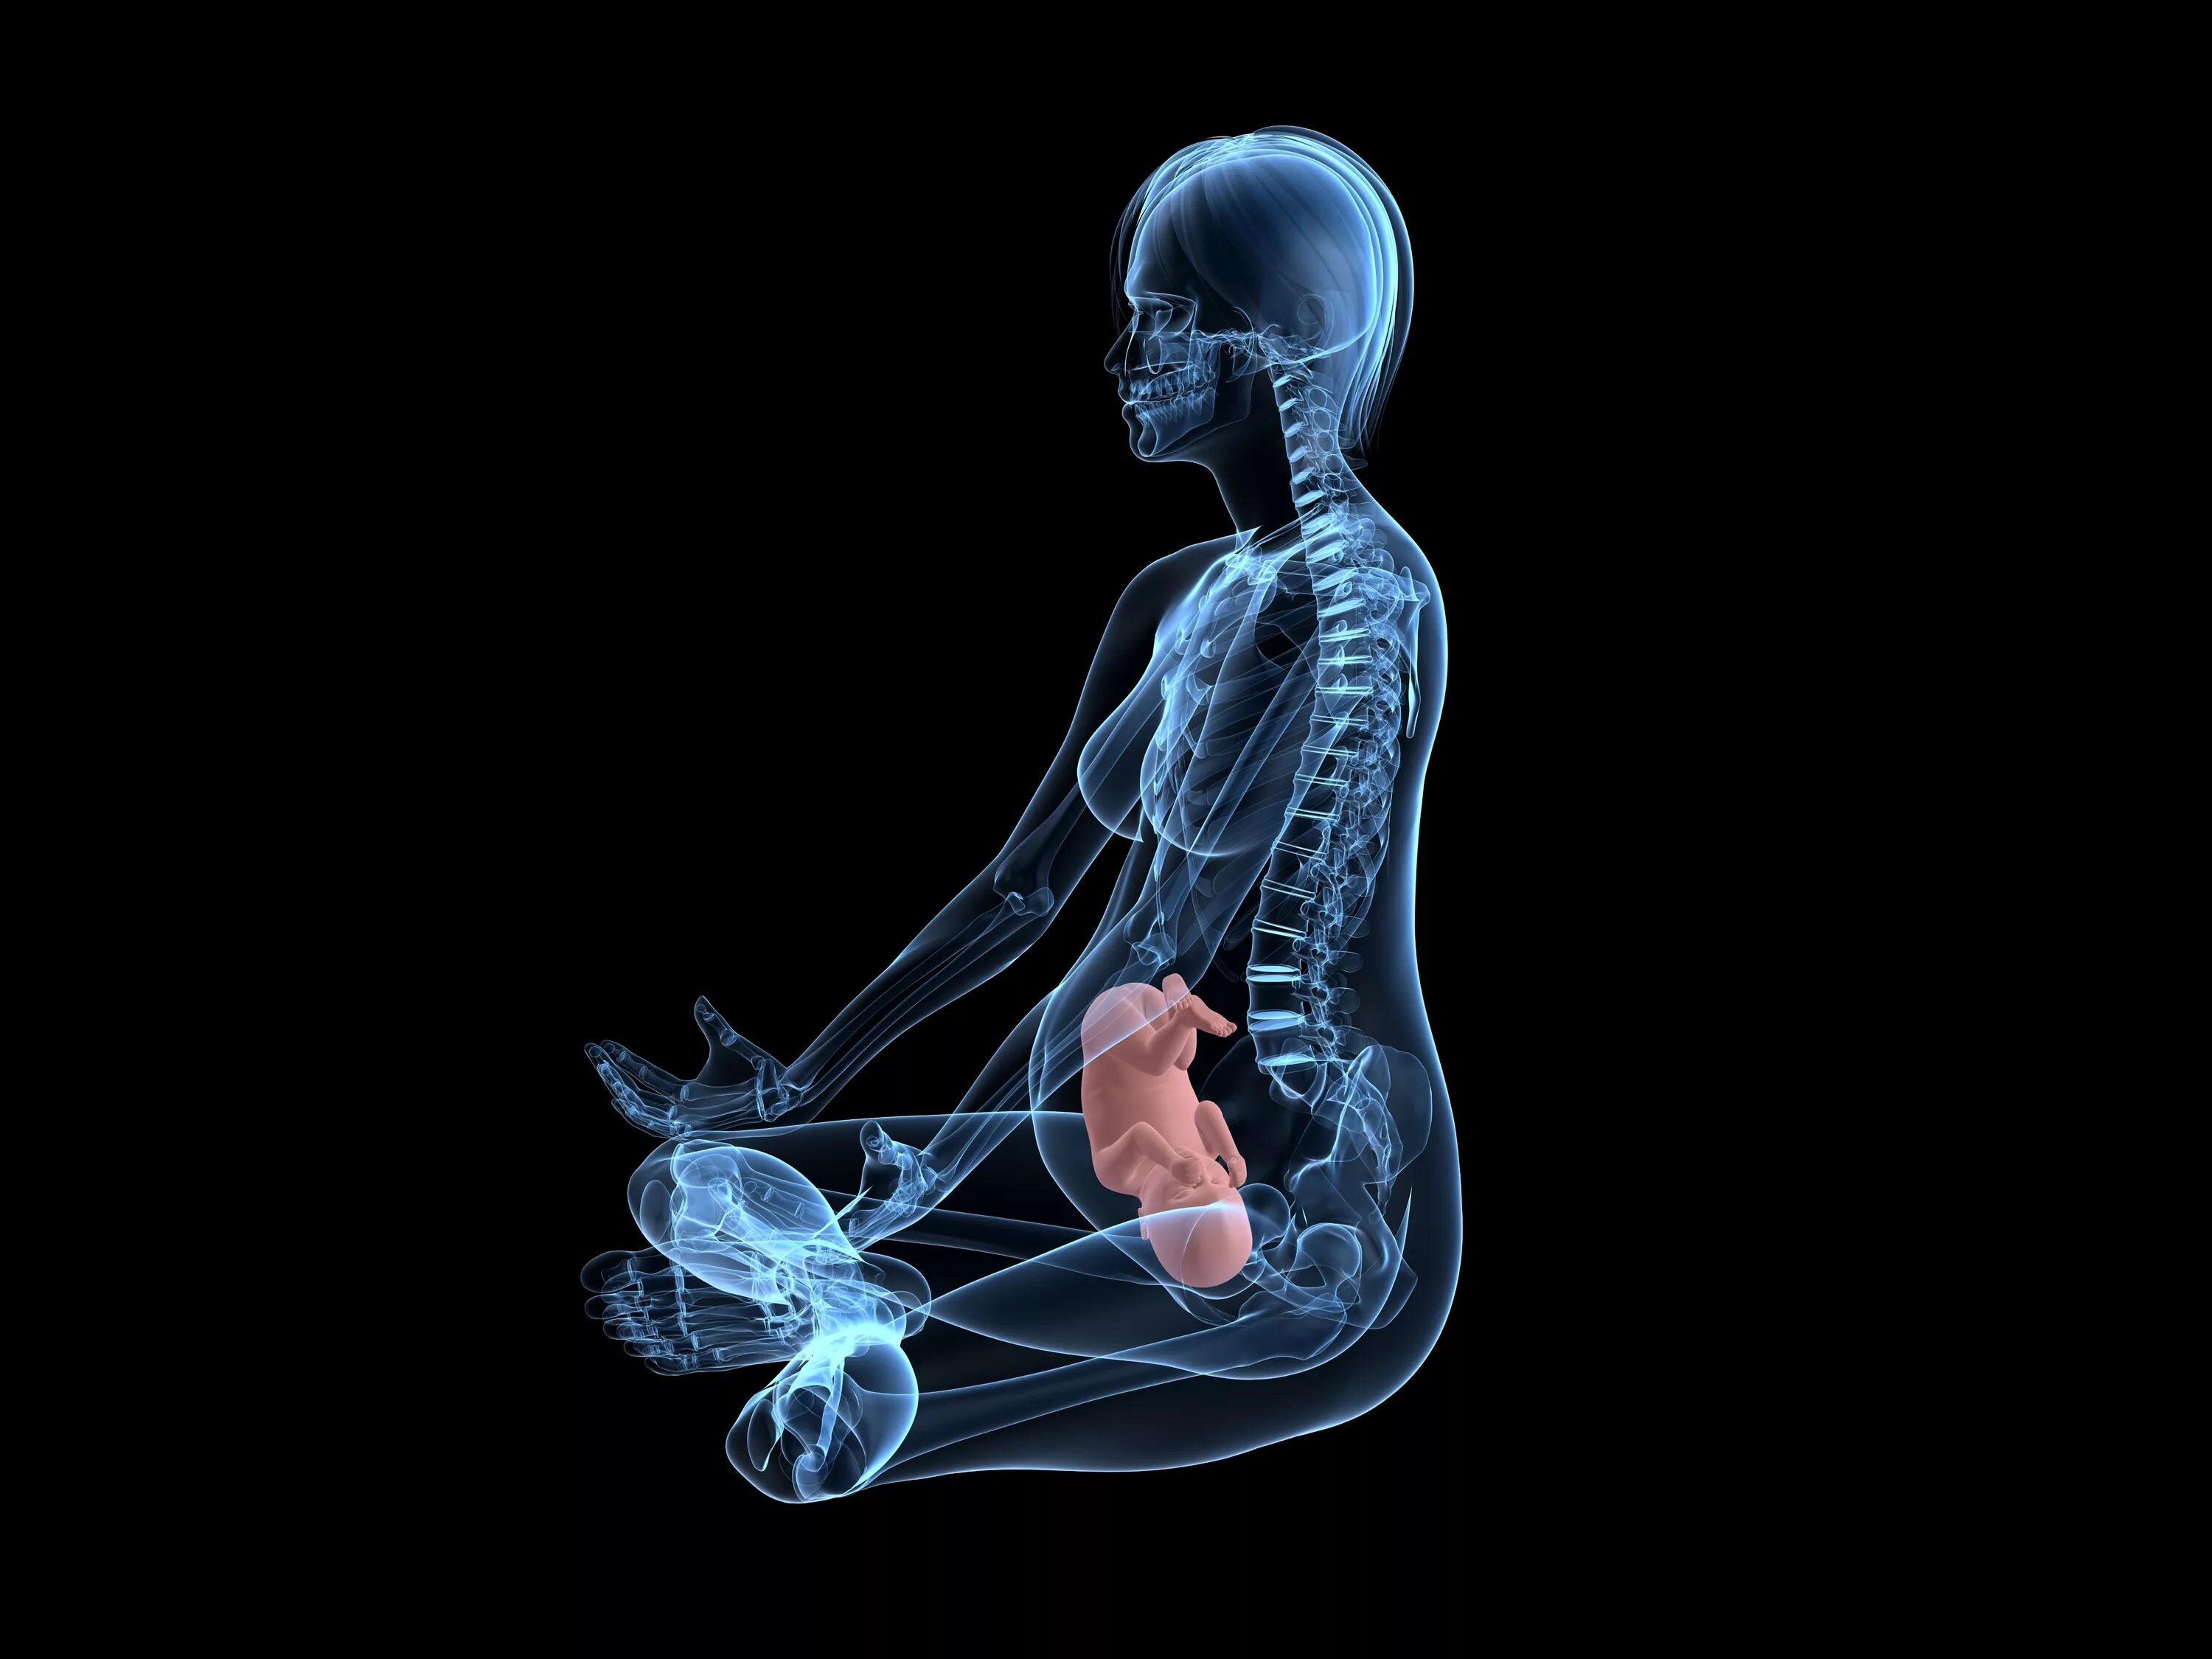

Делала рентген при беременности